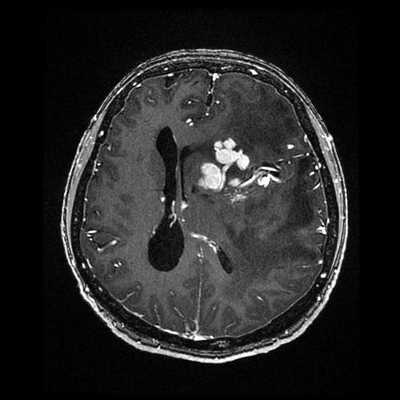

Пациентка У., 31 год, заболела в июне 2017 г., когда возникли диффузные, распирающие, труднопереносимые головные боли, не купируемые анальгетиками, усиливающиеся при малейшем движении головой. Головная боль сопровождалась тошнотой, рвотой. В течение недели боль нарастала: больная перестала заниматься повседневными обычными делами, постоянно лежала, продуктивный контакт был ограничен. Повышения температуры или других признаков инфекционного заболевания не наблюдалось. К концу недели стало беспокоить двоение при взгляде на любые расстояния. Движения глазных яблок сопровождались болью. Появились шаткость при ходьбе, неустойчивость, дрожание в руках. Утратила возможность передвигаться без поддержки. Проконсультирована окулистом, который обнаружил выраженные застойные явления на глазном дне и рекомендовал проведение магнитно-резонансной томографии (МРТ) головного мозга с последующей консультацией невролога. На МРТ головного мозга выявлен «конгломерат» множественных очагов в правой и, меньших размеров, на симметричном участке в левой лобно-теменной области (рис. 1, А).

Стандартное лабораторно-инструментальное обследование пациентки (биохимический анализ крови, электрокардиография, рентгенография органов грудной клетки, ультразвуковое исследование сосудов шеи) патологии не выявило. Осмотр офтальмолога: состояние глазного дна — диск бледно-розовый, границы четкие, калибр сосудов не изменен. МР-веносинусография и КТ-ангиография с венозной фазой: крупные вены и синусы не изменены, за исключением умеренного расширения корковых вен среднего и дистального сегмента справа (на уровне верхней анастоматической вены Тролярда) (рис. 2), что может служить признаком формирования коллатерального оттока.

Проведен консилиум с обсуждением клинико-нейровизуализационных и параклинических данных: на серии МР-томограмм головного мозга в паравентрикулярной области лобных долей, больше справа, определяются облаковидные конгломераты гидрофильно измененной мозговой ткани с мелкими очагами, напоминающими просяное зерно, и с полосчатыми вкраплениями, идентичными тромбозу мелких вен. Признаков масс-эффекта нет. Отдельные очаги накапливают контраст. Характеристика очагов, клинико-анамнестические данные и результаты обследований позволяют предположить у больной тромбоз мелких венозных сосудов (венул) глубоких отделов мозга. Рекомендована консультация гематолога.

По согласованию с гематологом назначен варфарин с коррекцией дозы в соответствии с цифрами международного нормализованного соотношения. На контрольной МРТ отмечается значительный регресс очагов (рис. 1, E, F). На фоне антикоагулянтной терапии пациентка смогла забеременеть и родить здорового ребенка. Рецидивов заболевания в течение 2 лет наблюдения не было, сохранялся описанный выше неврологический дефицит.